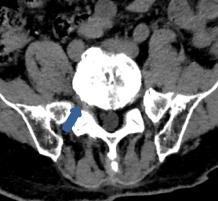

• 脊柱内镜侧后路联合减压术治疗腰神经根双卡综合征的临床疗效观察

2025, 31(12):25-32. DOI: 10.12235/E20250012

摘要 (122) HTML (46) PDF 10.14 M (90) 评论 (0) 收藏

摘要:目的 观察脊柱内镜侧后路联合减压术治疗腰神经根双卡综合征(DCS)的临床疗效、可行性、安全性和有效性。方法 回顾性分析2018年9月-2023年9月于该院就诊的50例腰椎退行性病变致腰神经根DCS患者的临床资料,根据手术方法不同,将患者分为观察组(37例)和对照组(13例)。观察组行脊柱内镜侧后路联合减压术治疗,对照组行非手术治疗。比较两组患者治疗前、治疗后1周、治疗后3个月、治疗后6个月和治疗后12个月的疼痛视觉模拟评分法(VAS)评分、Oswestry功能障碍指数(ODI)和日本骨科协会(JOA)评分。末次随访时,采用改良Macnab标准,评估临床疗效;采用腰椎MRI检查,评估椎间隙高度和椎间盘退变改良Pfirrmann分级。比较两组患者治疗的安全性(包括:并发症发生情况、复发情况和转手术治疗情况)。结果 50例患者均顺利完成治疗。两组患者术后VAS评分和ODI呈下降趋势,JOA评分呈升高趋势,观察组术后各时点VAS评分和ODI明显低于术前,且明显低于对照组,术后各时点JOA评分明显高于术前,且明显高于对照组,差异均有统计学意义(P < 0.05);观察组优良率为86.49%,明显高于对照组的76.92%,差异有统计学意义(P < 0.05);两组患者末次随访时,椎间隙高度和椎间盘退变Pfirrmann分级比较,差异均无统计学意义(P > 0.05)。两组患者围手术期均未出现神经损伤和脑脊液漏等严重并发症,观察组术后1例出现下肢放射性疼痛;观察组1例术后3个月出现腰椎间盘再突出;对照组有3例转手术治疗。结论 与非手术治疗相比,脊柱内镜侧后路联合减压术可更为安全、有效地缓解腰神经根DCS患者的疼痛,改善下肢功能,且早、中期临床疗效好。值得临床推广应用。